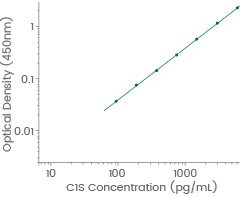

Human C1s antibody pair set: (Cat#: SEK10220)

Application: ELISA

Human C1s standard curve. Linear range: 93.75-6000 pg/mL. Image Credit: Sino Biological Inc.